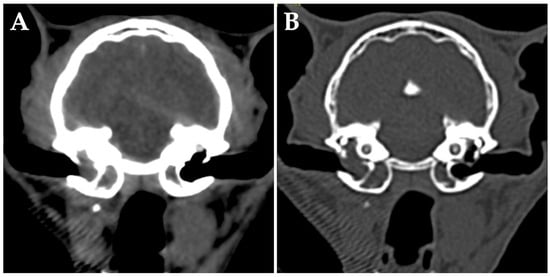

On day 42, whole-body CT without anesthesia or contrast media was performed for clinical staging. The middle ears appeared unchanged, but diffuse changes were observed in the liver (Figure 3A). Cytology of the liver lesions was not performed per the owner’s request. The tentative diagnosis was middle ear lymphoma with hepatic involvement, representing clinical stage 4 disease. After discussing the treatment plan with the owner, subcutaneous L-asparaginase was administered at 400 IU/kg (Kyowa Kirin, Tokyo, Japan). Prednisolone was continued at 5 mg/cat/day.

On day 56, right eyelid opening had improved. Follow-up whole-body CT without anesthesia or contrast media showed that the dorsolateral lesion of the right tympanic bulla had disappeared, the hepatic lesions were obscured (Figure 3B), and liver swelling had improved. L-asparaginase was evaluated as effective, and a second dose was administered.

Figure 3. Transverse computed tomography (CT) (without anesthesia or contrast media) of the abdomen at the level of the liver on day 42. (A) Numerous hypo-attenuating nodular lesions are seen in all lobes of the liver (arrowheads). (B) CT image of the same position on day 56. The hepatic lesions are obscured.